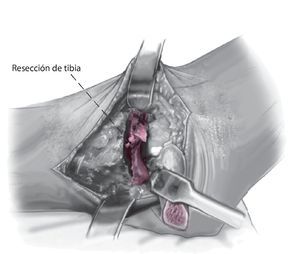

Fig. 6 Realice la osteotomía en la tibial distal perpendicular al eje tibial. Cuando se realiza de medial a lateral, el paquete neurovascular posteromedial es visible y se puede supervisar. La resección de la tibia debe ser lo menor posible para evitar el acortamiento de la extremidad.